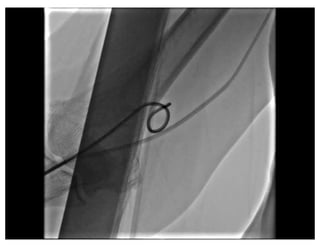

Radial Loop

Patel’s  Atlas  of  Transradial  intervention  – The Basics. 2007

Traversing a radial loop

Patel’s  Atlas  of Transradial  intervention  – The Basics. 2007 Traversing a radial loop